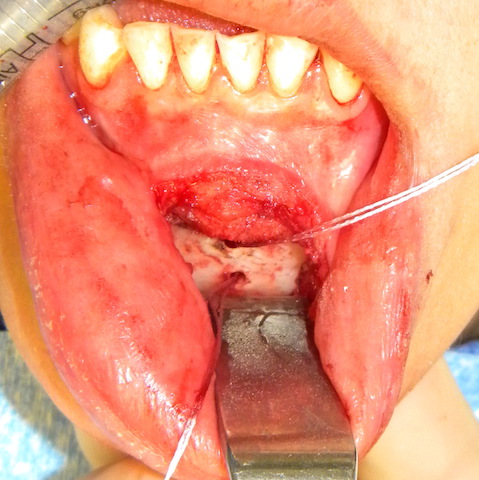

mentalis muscle resuspension intraop Dr Barry Eppley Indianapolis